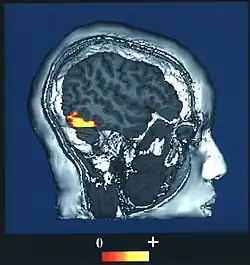

Brain imaging studies typically show a great deal of activity in an area of the temporal lobe known as the fusiform gyrus, an area also known to cause prosopagnosia when damaged (particularly when damage occurs on both sides). This evidence has led to a particular interest in this area and it is sometimes referred to as the fusiform face area (FFA) for that reason.[10]

The fusiform face area (BA37— Brodmann area 37) is located in the lateral fusiform gyrus. It is thought that this area is involved in holistic processing of faces and it is sensitive to the presence of facial parts as well as the configuration of these parts. The fusiform face area is also necessary for successful face detection and identification. This is supported by fMRI activation and studies on prosopagnosia, which involves lesions in the fusiform face area.[34][35][36][37][38]

During face perception, major activations occur in the extrastriate areas bilaterally, particularly in the above three areas.[34][35][38] Perceiving an inverted human face involves increased activity in the inferior temporal cortex, while perceiving a misaligned face involves increased activity in the occipital cortex. No results were found when perceiving a dog face, suggesting a process specific to human faces.[41] Bilateral activation is generally shown in all of these specialized facial areas.[42][43][44][45][46][47] However, some studies show increased activation in one side over the other: for instance, the right fusiform gyrus is more important for facial processing in complex situations.[36]

BOLD fMRI mapping and the fusiform face area

The majority of fMRI studies use blood oxygen level dependent (BOLD) contrast to determine which areas of the brain are activated by various cognitive functions.[48]

One study used BOLD fMRI mapping to identify activation in the brain when subjects viewed both cars and faces. They found that the occipital face area, the fusiform face area, the superior temporal sulcus, the amygdala, and the anterior/inferior cortex of the temporal lobe all played roles in contrasting faces from cars, with initial face perception beginning in the fusiform face area and occipital face areas. This entire region forms a network that acts to distinguish faces. The processing of faces in the brain is known as a "sum of parts" perception.[49]